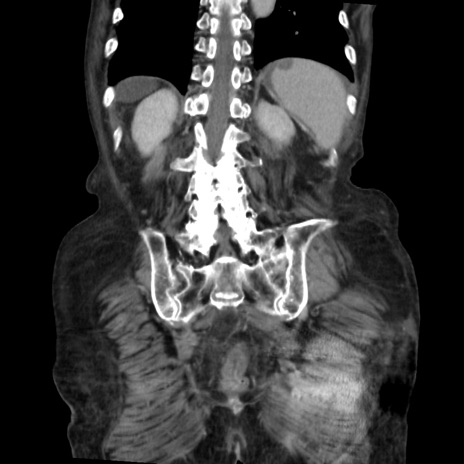

症例31(冠状断像)

【症例】80歳代 女性

【主訴】腹部膨満感

【現病歴】他院にて肝硬変にてフォロー中。1週間前から便秘、腹部膨満感、臍部腫瘤あり受診となる。

【既往歴】肝硬変

【身体所見】腹部膨隆あり、皮膚変化なし、疼痛なし。

【データ】WBC 4600、CRP 0.25